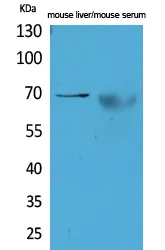

alpha 1 Fetoprotein Rabbit Polyclonal Antibody

Cat: APRab00486

Size1:50μl Price1:$150

Size2:100μl Price2:$280

Size3:500μl Price3:$1200

Size2:100μl Price2:$280

Size3:500μl Price3:$1200